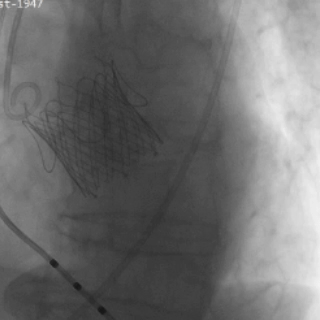

瓣膜功能、形态良好,未见反流